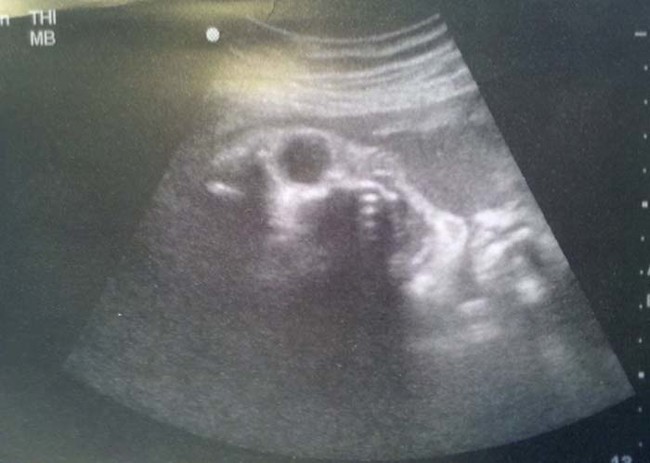

เดี๋ยวนี้ยามตั้งครรภ์คุณแม่เกือบทุกคนก็นิยมอุ้มท้องป่อง ๆ ไปให้คุณหมอทำอัลตราซาวด์ จะได้เช็กดูว่าเจ้าตัวน้อยข้างในอยู่สบายแข็งแรงดีหรือเปล่า แถมยังได้จะเห็นไปหน้าเค้าโครงใบหน้าลาง ๆ ของเจ้าหนูด้วย ดูแค่เงาก็เดาไปกันใหญ่แล้วว่าเหมือนใครมากกว่ากัน จนอดใจไม่ไหวอยากรีบคลอดออกมาให้เห็นหน้าลูกน้อยตัวจริงเร็ว ๆ แต่ถ้ามาเจอ 13 รูปอัลตราซาวด์สุดสยอง ที่เรานำมาฝากจากเว็บไซต์ boredomtherapy เหล่านี้เข้าไปหน่อยล่ะก็... บางทีคุณอาจไม่แน่ใจแล้วล่ะว่า นี่ใช่ลูกฉันจริงหรือเปล่า !!

ถึงจะรักเด็กแค่ไหน แต่ถ้าคุณขวัญอ่อนเราขอเตือนกว่าอย่าเลื่อนลงไปดูดีกว่านะ...